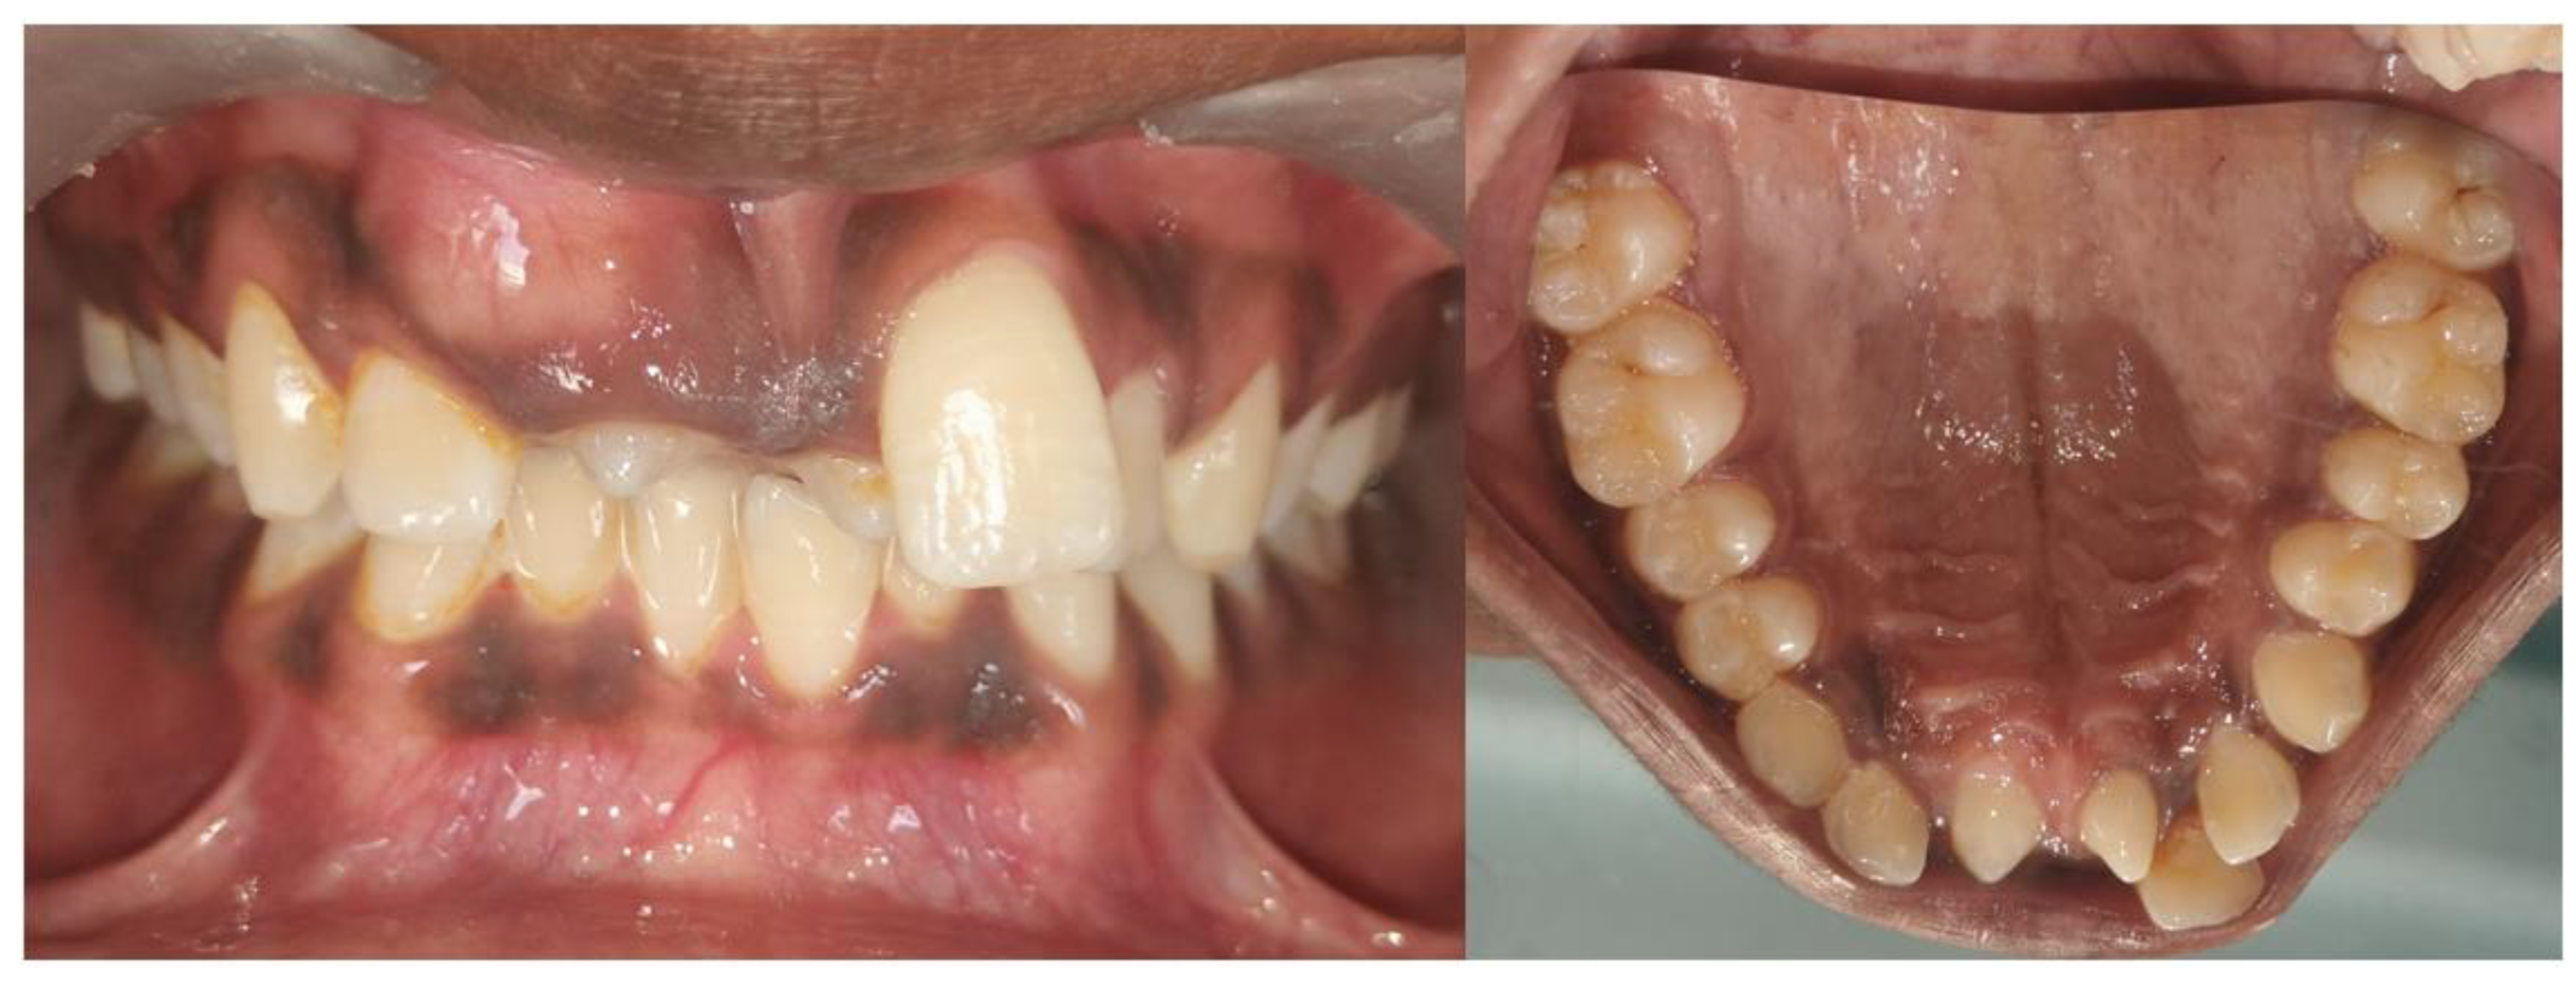

Figure 1. Bilateral mesiodens in the maxillary anterior region. Bilateral mesiodens is a rare entity; studies suggest that both environmental influences and genetic factors can heighten the activity of the dental lamina, resulting in the formation of an additional tooth or teeth [1]. A 14-year-old male patient accompanied by his mother was admitted to the department of pediatric dentistry with a primary complaint of unaesthetic appearance in the upper front tooth region of the jaw and wanted to have this corrected. Upon clinical examination, it was found that the right maxillary central incisor was clinically absent, indicating possible impaction. Malalignment of the anterior teeth with crowding and spacing was observed. Mild rotation of upper left central incisor teeth with a noticeable deviation of the midline was seen. Also, bilateral mesiodens were noted in the maxillary midline region, positioned palatally with partially erupted crowns. The patient did not provide any relevant medical history associated with mesiodens. Mesiodens is the most common type of supernumerary tooth, occurring in the anterior maxillary midline, and is classified as either eumorphic (resembling a normal incisor) or dysmorphic (having an irregular shape). These additional teeth often remain unerupted and can cause dental complications such as impaction, delayed eruption of permanent teeth, and crowding [2]. According to the literature, it has been reported that there is 89.7% prevalence for single mesiodens and 10.3% for bilateral cases [3]. The present case exhibits dental malalignment attributed to the presence of bilateral mesiodens that has contributed to the impaction of the right maxillary central incisor and resulted in crowding and the rotation of the adjacent teeth. Such malalignment may hinder esthetics, function, and proper oral hygiene. Management typically involves surgical extraction of the mesiodens, followed by orthodontic intervention to guide the eruption and alignment of the impacted or displaced teeth. Thus, an early diagnosis through clinical examination and radiographic evaluation is crucial to prevent long-term complications.